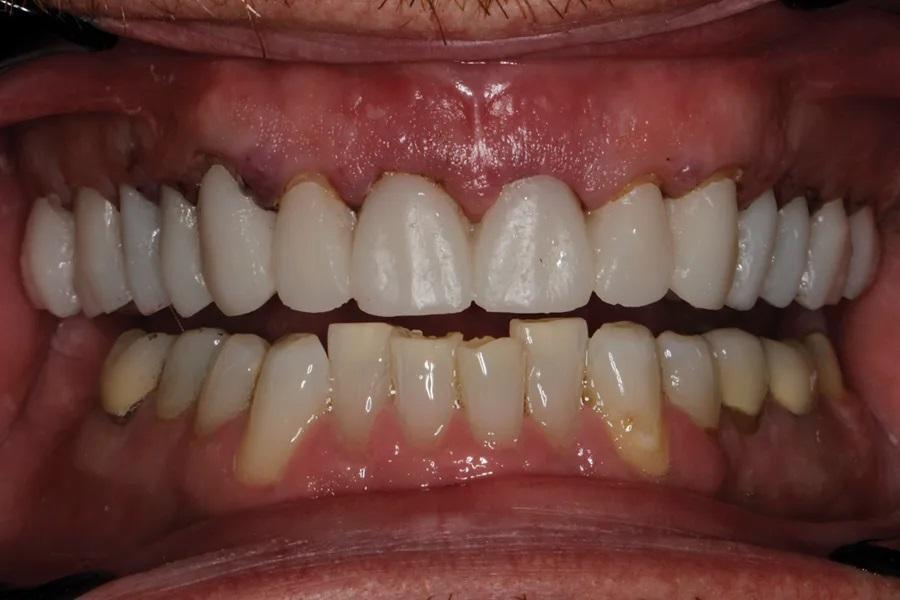

Мужчина, 45 лет. Основная жалоба — неловкость при улыбке из-за коротких, деформированных и измененных в цвете зубов. Обследование выявило гингивит с соответствующей потерей прикрепления, множественные кариозные поражения, износ зубов и реставраций (Фото 1 – Фото 3). Зафиксирован ограниченный паттерн жевания (ОПЖ), что определило умеренный функциональный риск и необходимость учета окклюзии в плане лечения.